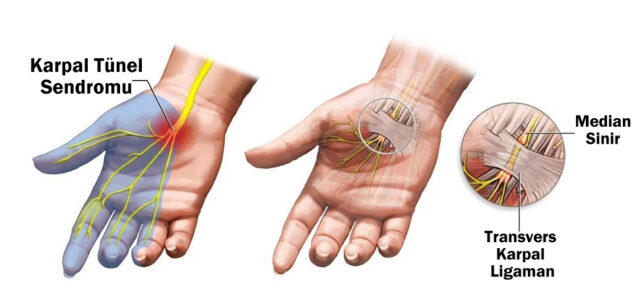

Karpal Tünel Sendromu Nedir?

Karpal Tünel Sendromu Nedir?